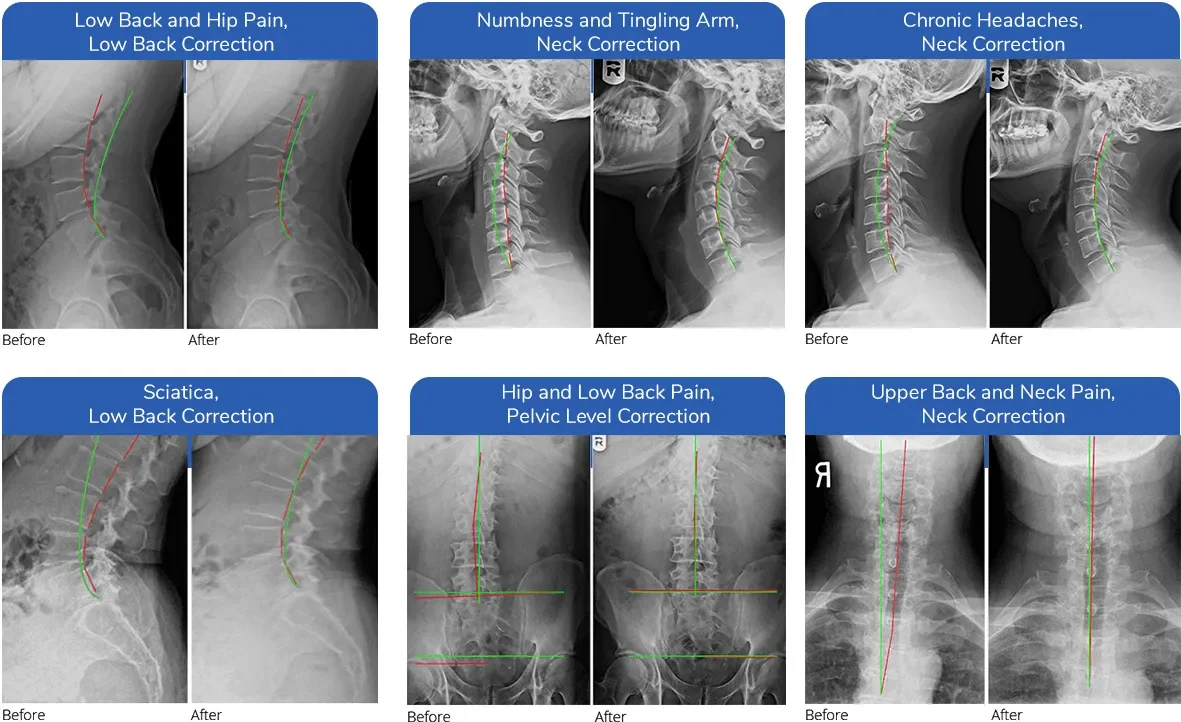

This intensive phase follows relief care, typically involving frequent visits over weeks to months, with progress tracked via x-rays and posture assessments.

• Corrected posture and spinal curves

• Notably, some studies have reported improvements in spinal curvature of 30-40% following corrective chiropractic interventions, although individual results may vary.